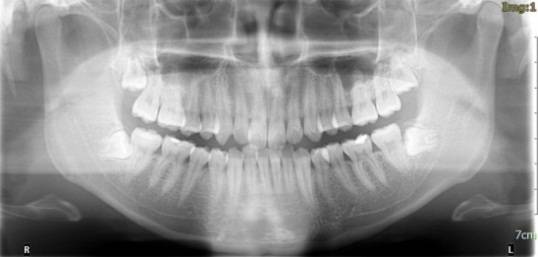

放射检查:一般包括X线头影测量片、曲面体层片和CBCT(锥束CT)。有时还包括其他放射检查,比如螺旋CT等。通过放射检查,医生可以看到骨骼及牙齿的形态、位置及发育状况,以及是否有牙体、根尖周、牙周疾病等,从而评估是否需要正畸治疗、进行何种治疗。

头影测量片(上)、曲面体层片(中)和锥束CT(下)